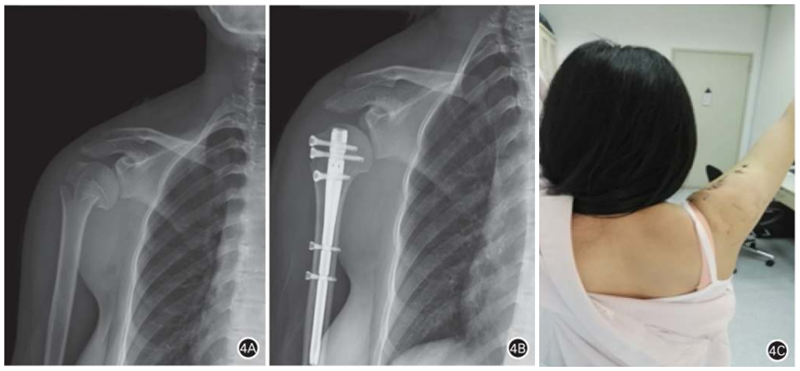

目前,临床使用近端直型锁定型肱骨近端交锁髓内钉治疗肱骨近端骨折。Hessmann等采用多枚交锁螺钉多方向锁定固定肱骨近端,并且设计了“钉中钉”,目的是更好地固定肱骨头。第三代肱骨近端髓内钉可治疗所有类型的肱骨近端骨折。微创髓内钉的优点:(1)对软组织损伤更小,最大限度保留了骨折后残存的血供;(2)术后疼痛程度较轻,功能恢复较快(图4);(3)髓内中心固定肱骨近端髓内钉对抗内翻应力优于髓外偏心固定的肱骨近端锁定钢板(图5)。髓内钉理论上的优势是否能在临床实践中得到体现尚需临床循证医学证据支持。

图4 患者女,30岁,右肱骨近端两部分外科颈骨折后行闭合复位髓内钉固定。 A. 术前正位 X 线片示右肱骨近端两部分外科颈骨折;B. 闭合复位髓内钉固定;C. 术后 2周,肩关节上举120°左右,恢复基本生活自理能力